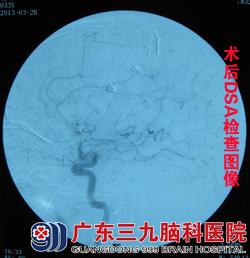

据了解,谭先生于3月19日凌晨1时许突发头痛、右侧肢体乏力。当地医院CT检查提示左侧额顶叶脑出血并破入脑室,对症治疗后头痛减轻,右侧肢体乏力好转。为求进一步治疗而来到广东三九脑科医院。入院行MRA、CTA检查提示动静脉畸形合并动脉瘤,经专家讨论决定为其行介入栓塞手术治疗。3月28日,谭先生顺利接受了手术治疗,术中见左侧大脑前动脉额内后动脉多发动脉瘤,呈串珠样,囊状,左侧额叶动静脉畸形。分别用弹簧圈填塞动脉瘤、外科胶栓塞动静脉畸形,术程非常顺利,术后给予抗凝血、抗感染、营养支持等治疗。术后经过两周的康复锻炼,谭先生右侧肢体肌力恢复正常,得以康复出院。